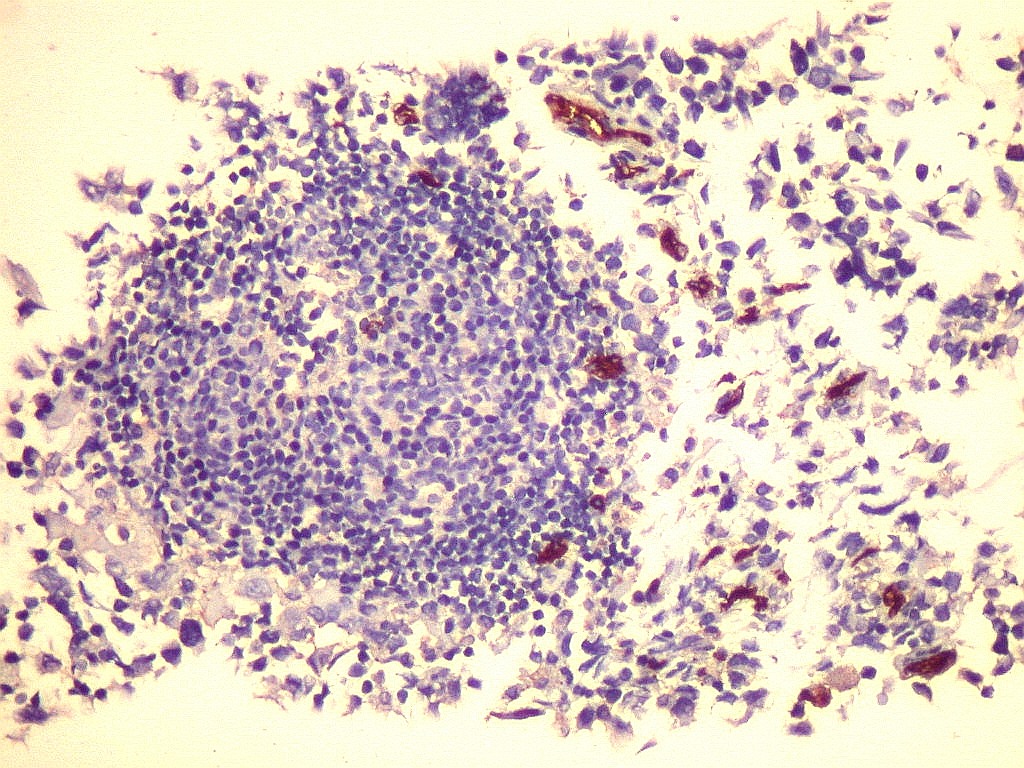

Tumor teratóide rabdóide atípico de III ventrículo.

7.  CD3, CD20, CD68, CD34

CD20.      Positivo nos linfócitos B, negativo nas células neoplásicas.  No folículo linfóide presente na amostra, as células centrais são de linhagem T, e as células B concentram-se na periferia.  Células do ATRT não se marcam.

CD68.        Marca numerosos macrófagos no tumor, indicando alto turnover celular e  morte de muitas células neoplásicas, que são fagocitadas pelos macrófagos.